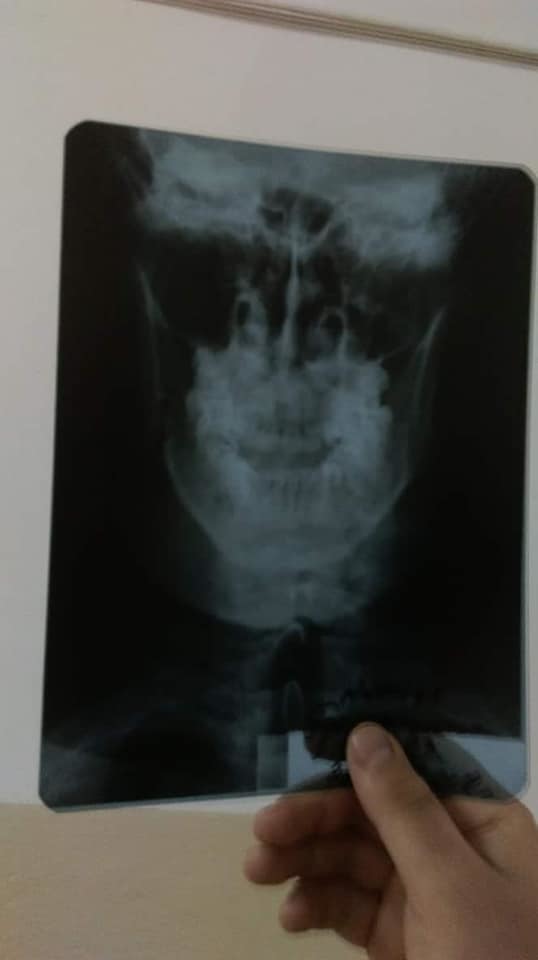

Отмечается, что в результате конфликта мужчине сломали челюсть. Более того, побоям также подверглись его товарищ с супругой. Об инциденте написал друг пострадавшего, также участник АТО Виталий Мельниченко на своей странице в Facebook.

На место происшествия были вызваны правоохранители. Пострадавшие сняли побои и написали соответствующее заявление. У ветерана АТО Бородиенко диагностировали перелом челюсти, в связи с чем 23 июля он был прооперирован.